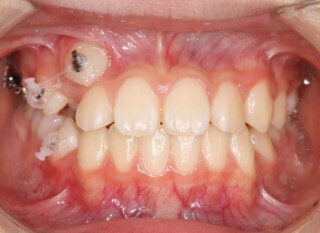

小児期第二段階

開始時